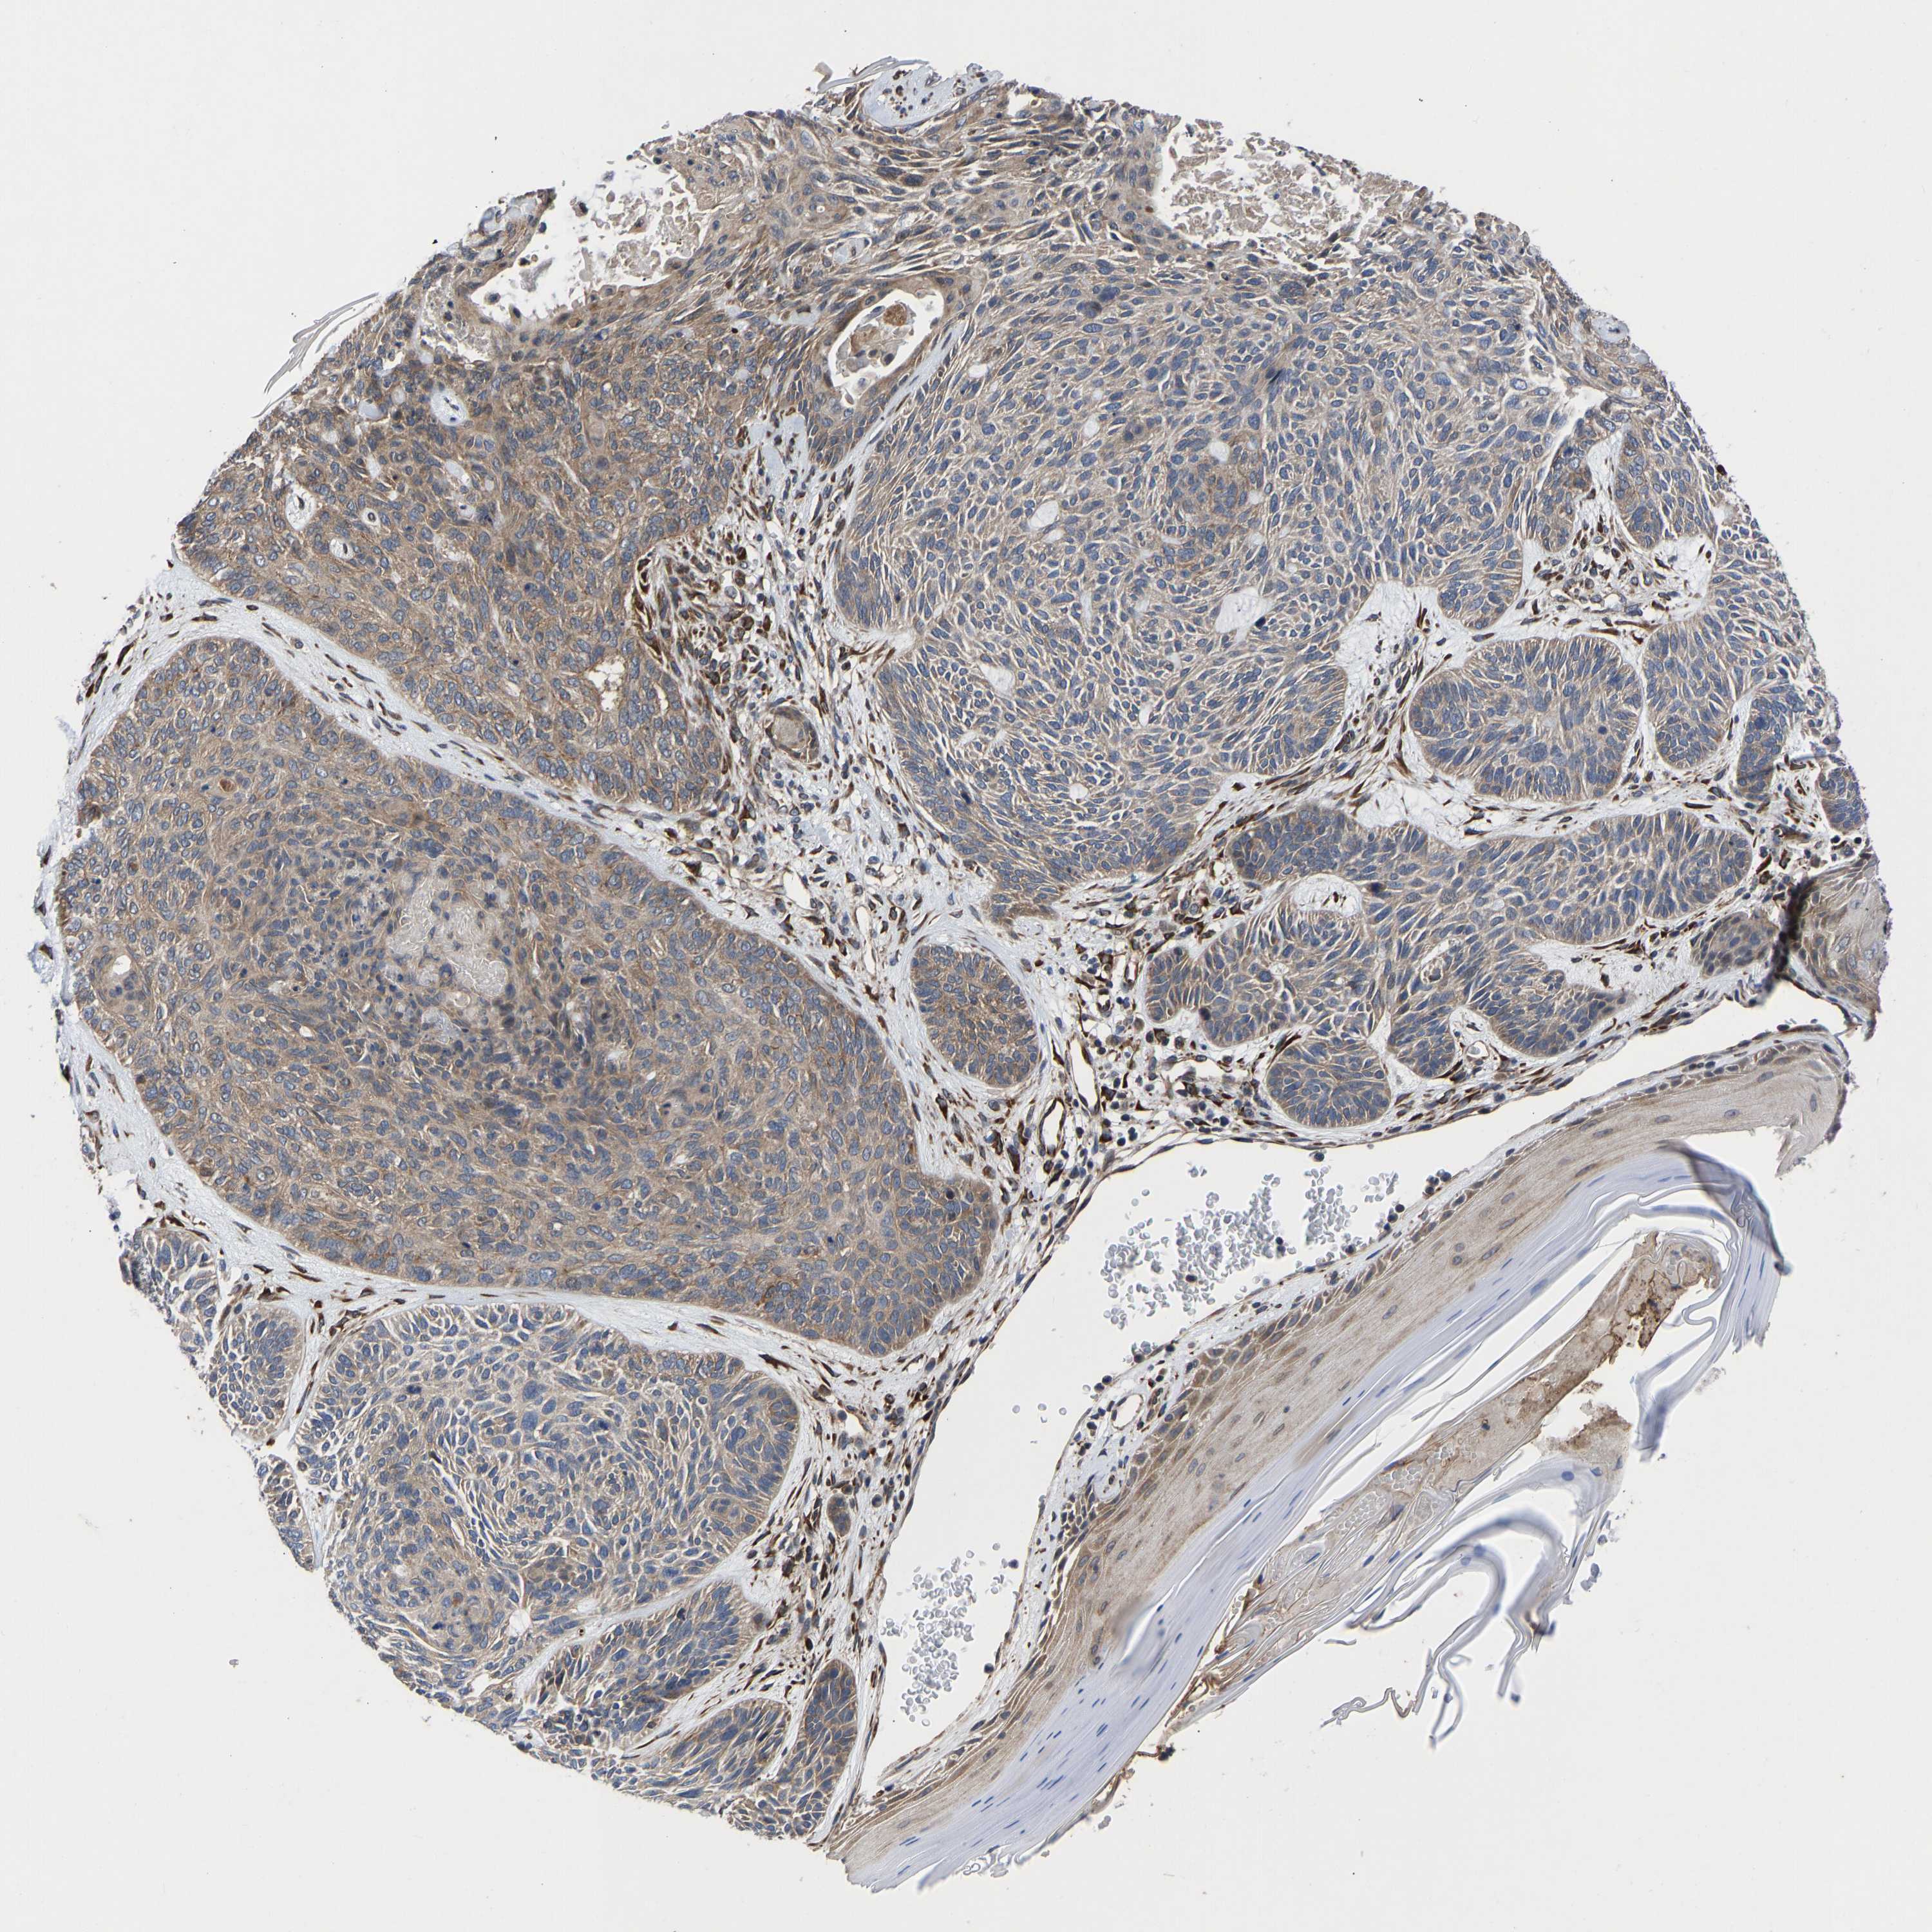

SKIN CANCER - Protein expressioni

A mouse-over function shows sample information and annotation data. Click on an image to view it in a full screen mode. Samples can be filtered based on level of antibody staining by selecting one or several of the following categories: high, medium, low and not detected. The assay and annotation is described here.

Antibody staining in the annotated cell types in the current human tissue is reported as not detected, low, medium, or high, based on conventional immunohistochemistry profiling in selected tissues. This score is based on the combination of the staining intensity and fraction of stained cells.

Each image is clickable and will lead to virtual microscopy that enables deeper exploration of all samples and also displays staining intensity scores, fraction scores and subcellular localization as well as patient and tissue information for each sample.

Antibody HPA017883

Intensity

Strong

Moderate

Weak

Negative

Quantity

>75%

75%-25%

<25%

None

Location

Nuclear

Cytoplasmic/membranous

Cytoplasmic/membranous,nuclear

Basal cell carcinoma

Squamous cell carcinoma, NOS

Squamous cell carcinoma, metastatic, NOS